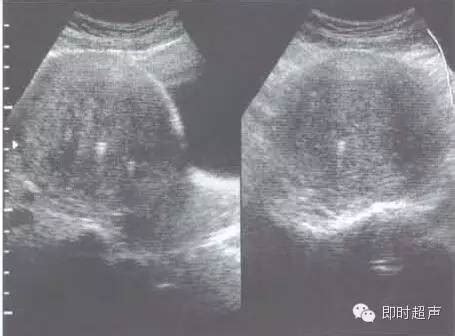

子宫肌腺症多发生在生育年龄之经产妇,少数发生在未接受过任何子宫手术之未产妇,此可能与其子宫肌肉层细胞的特殊化生过程有关。子宫肌腺症的患者有很大的比例会有经痛和经血量过多的症状,骨盆腔触诊(内诊)检查可发现一稍微增大、对称的子宫,且通常会有触痛反应。一般超音波无法区分局部的子宫肌腺瘤或子宫(平滑肌)肌瘤,利用彩色都卜勒超音波可侦测其血管血流分布,增加对子宫肌腺瘤和子宫肌瘤的鉴别诊断能力。

【子宫腺肌症的临床表现及诊断】约30%患者无任何临床子宫腺肌症的症状。凡30岁以上的经产妇,出现经量增多、经期延长以及逐年加剧的进行性痛经,检查时子宫呈均匀性增大或有局限性结节隆起,质硬而有压痛,经期压痛尤为显著时,应首先考虑为子宫腺肌症。B型超声检查可在肌层中见到种植内膜所引起的不规则回声增强。